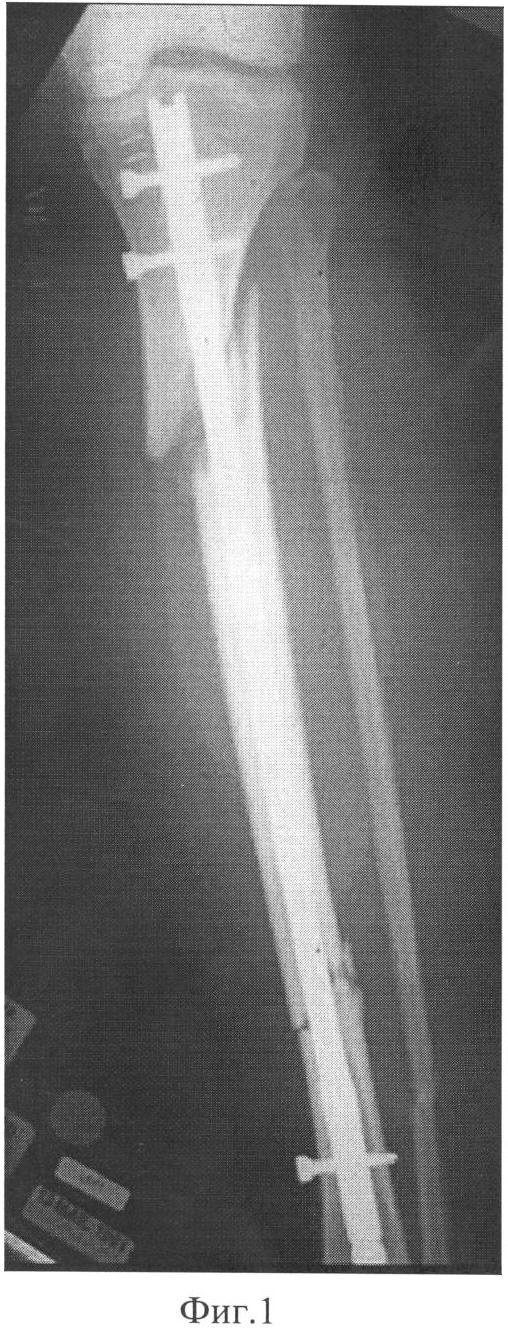

– при переломах проксимального отдела большеберцовой кости часто возникают проблемы вальгусной и антекурвационной деформации отломков (на Фиг.1 – типичная вальгусная деформация, на Фиг.2 – типичная антекурвационная деформация и смещение отломка кзади), что может потребовать операции при полуразогнутом положении колена для уменьшения тяги четырехглавой мышцы бедра, при этом требуется расширенный до 7-8 см доступ с артротомией, чтобы обеспечить прохождение стержня рядом с надколенником по межмыщелковой борозде бедренной кости при тенденции к прохождению интрамедуллярного гвоздя по направлению к задней стенке короткого проксимального фрагмента, а не по его продольной оси, необходимо использовать введение отклоняющего (Poller) винта, чтобы, отклонившись от него, гвоздь не был направлен к задней стенке фрагмента, что увеличивает время операции;